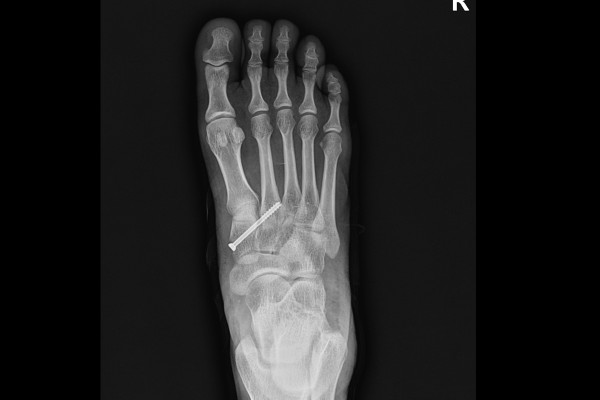

수술이 잘 마무리 되었고, 보행은 수술 후 반깁스 착용 후 발 앞쪽부위를 제외한 뒷꿈치로 바로 가능합니다.(앞쪽에 힘을 주게 되면 스크류가 부러질 위험이 있기 때문에 제거 전까지는 조심해야 합니다.) 수술 후 4~6주간은 반깁스를 착용하고서 조심해주시다가, 4주에서 6주가 지난 시점에 스크류를 제거하고 나면 발을 다 디디고 걷는 것이 가능합니다.

b1d6a7ed823268faf8290a31a2d8a8bb_1765960277_2284.jpg

4~6주가 지난 시점에서 스크류를 제거한 X-RAY 사진입니다. 스크류를 제거했음에도 벌어짐 없이 잘 고정되어 있는 것이 확인됩니다. 이후 환자분께서는 수술 후 3개월이 지난 시점에서 내원해주셨고, 통증 등 증상이 아예 없고, 현재 운동도 복귀하여 축구, 수영 등 모든 활동을 하고 계시다며, 매우 만족해하셨습니다.